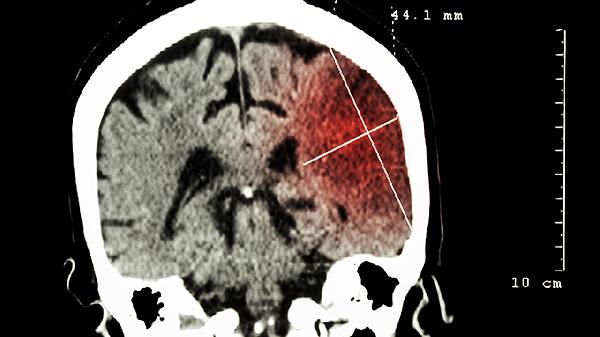

脑内脱髓鞘改变是怎么回事

脑内脱髓鞘改变可能由遗传因素、免疫异常、感染、代谢障碍、中毒等原因引起,可通过药物治疗、康复训练、生活方式调整、心理干预、手术治疗等方式改善。建议及时就医,在医生指导下进行针对性干预。